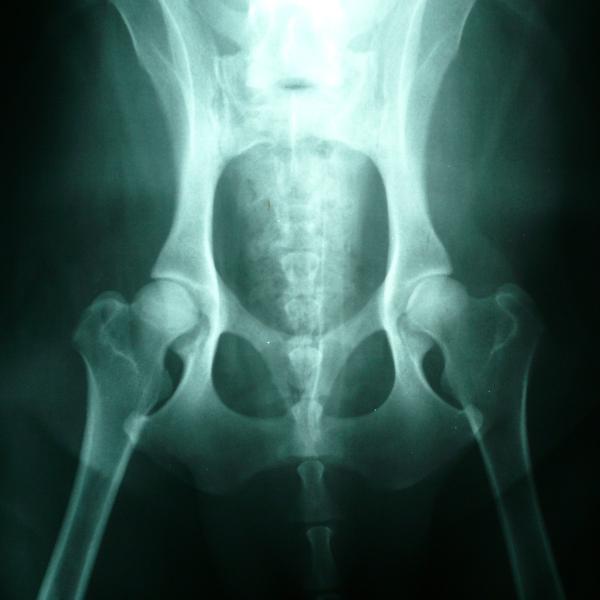

Displasia de cadera, principal causa del fallo en las patas traseras de los gatos

Aunque no es tan habitual como en los perros, existen casos con este padecimiento. Una displasia de cadera en felinos tiende a ser hereditaria y consiste en un desarrollo anormal de los huesos de la cadera y el fémur, que provoca desplazamiento y daño en ambas articulaciones de la cadera o en una sola según cada caso. Este trastorno puede aparecer desde muy pequeño y con el paso del tiempo tiende a dislocarse mucho más ocasionando pequeñas fracturas o daños en los cartílagos de la parte inferior del gato. No obstante, algunas veces puede aparecer cuando el gato es más mayor, por causas que normalmente no son genéticas.

Los síntomas más comunes cuando se presenta de displasia de cadera en gatos son:

• Cojera

• Dolor en las patas traseras

• No salta ni corre

• Crujido proveniente de la cadera

Si además de la debilidad presenta estos síntomas, es importante acudir con el veterinario.